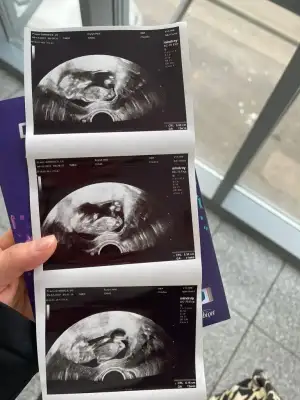

dr soylemeden siz gorun genital nub teorisi ( bebegin cinsiyeti)

Benim de ray may kalmayacak galiba. Tek kesede 2 bebek gördük bu haftaAy tesadüfe bak önceden demiş oldum o zaman hayırlı olsun ikimizde saglikla kucağınıza alın inşallah.mucizelerin kadınısınraydan dahada çıktı diyelim oturmaktan ziyade

Aman Allahım ciddimisinBenim de ray may kalmayacak galiba. Tek kesede 2 bebek gördük bu haftadr haftaya netleştirelim dedi. Hayırlısı

Valla ben bebeği bile göremiyorum şu an. Ben bilmiyorum yorumlamayı.Eki Görüntüle 3216105 banada bakarmısınız

6-9 haftalık ultrason fotosu gönderirseniz bakabilirim böyle anlamıyorum maalesefMerhaba banada tahminde bulunabilirmisiniz

Banada bakarmısınız 7+6 karından6-9 haftalık ultrason fotosu gönderirseniz bakabilirim böyle anlamıyorum maalesef

Canım ben üç çizgi gördüm kıza benzettim hayırlısı olsunEki Görüntüle 3216105 banada bakarmısınız